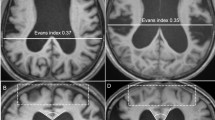

Each group of animals exhibited considerable ventriculomegaly throughout the study period (Fig. 1; see also [42]) that was accompanied by significant changes in various white matter regions (Fig. 2; Table 1). No significant differences were noted between the right and left sides of the optic chiasm, optic tract, or internal capsule, and therefore left and right data points for each of these regions were pooled.

Diffusion tensor parameters for the optic chiasm (black), optic tract (light gray), corpus callosum (white), and internal capsule (dark gray) within control, early, and late groups <6 (acute) and ≥6 (chronic) weeks after reservoir placement. a FA fractional anisotropy. FA in the corpus callosum (CC) in the acute phase (CC obliterated and not available for analysis in the chronic phase) was significantly decreased in both the early and late groups compared with controls (*p = 0.0008). Likewise, in the optic chiasm and tract FA of the chronic phase was significantly decreased in the late group compared with controls (• p < 0.05). In contrast, in the internal capsule FA was significantly increased in the chronic phase compared with the acute phase in all groups (^p < 0.05). b Axial diffusivity (AD) in the corpus callosum was significantly increased compared with controls (*p < 0.05) in the acute phase; this pattern of an AD increase in the acute phase compared with controls was repeated in the internal capsule (^p < 0.05). c Radial diffusivity (RD) was significantly increased compared with controls in the corpus callosum (*p < 0.01) and significantly decreased in the optic tract in the early group (• p < 0.05). d Mean diffusivity (MD) in the corpus callosum was significantly increased in the early and late groups in the acute phase compared with controls (*p < 0.01). Overall, these results indicate that white matter integrity in both reservoir groups was compromised during the progression of ventriculomegaly, with the corpus callosum appearing most vulnerable and the optic system the most resilient